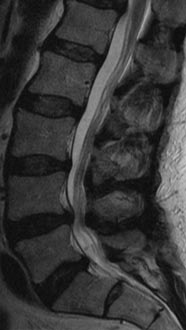

61 year old man with previous history of microdiscectomy at L4-5 presenting with severe back pain with radiating pain down the right leg with weakness. He had a massive disc extrusion on the right side. Options included revision discectomy vs. L4-5 revision decompression and fusion with transforaminal lumbar interbody fusion (TLIF). Patient did not want to go through the pains of recurrent disc herniation again and elected for the fusion.